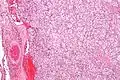

On microscopic inspection, the tumor cells are readily recognized. Individual tumor cells are polygonal to oval and are arranged in distinctive cell balls, called Zellballen.[8] These cell balls are separated by fibrovascular stroma and surrounded by sustentacular cells.

With immunohistochemistry, the chief cells located in the cell balls are positive for chromogranin, synaptophysin, neuron specific enolase, serotonin, neurofilament and Neural cell adhesion molecule; they are S-100 protein negative. The sustentacular cells are S-100 positive and focally positive for glial fibrillary acidic protein. By histochemistry, the paraganglioma cells are argyrophilic, periodic acid Schiff negative, mucicarmine negative, and argentaffin negative.